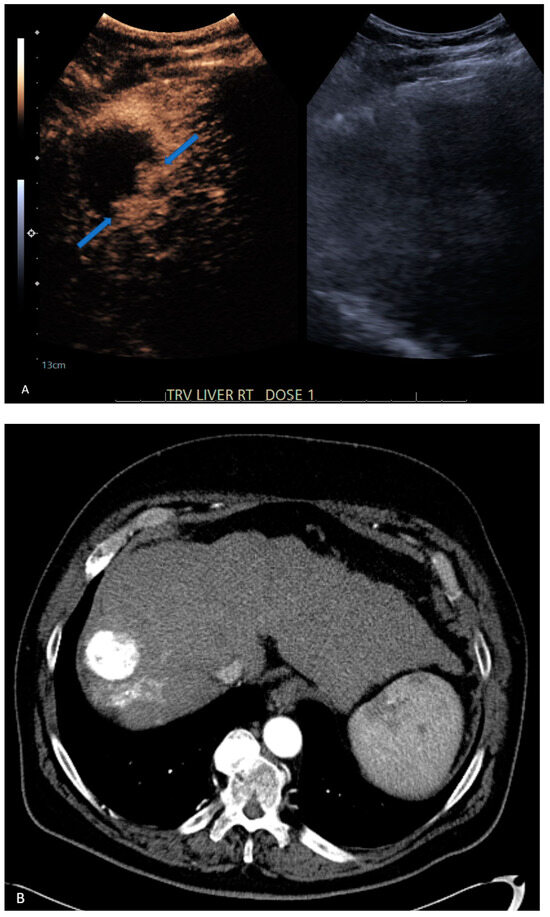

| 4 | CT | Target | LR-treated | CEUS called residual tumor (Figure 1), follow-up CT confirmed treated tumor |